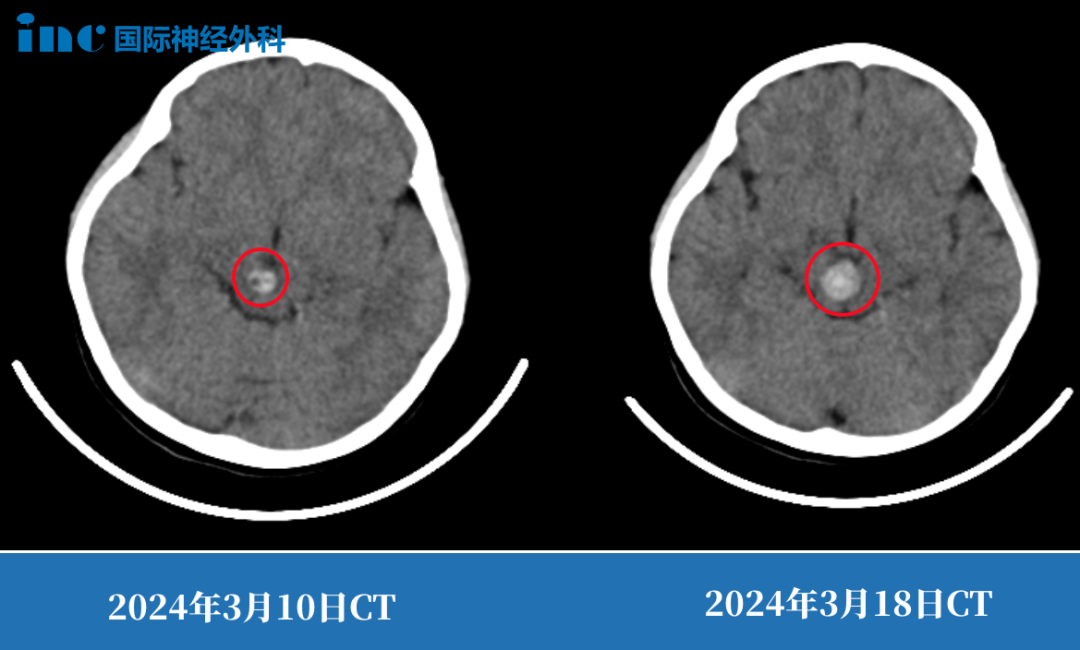

第二次出血意味着病情恶化,这一点在间隔仅8天的CT检查对比中足以证明。